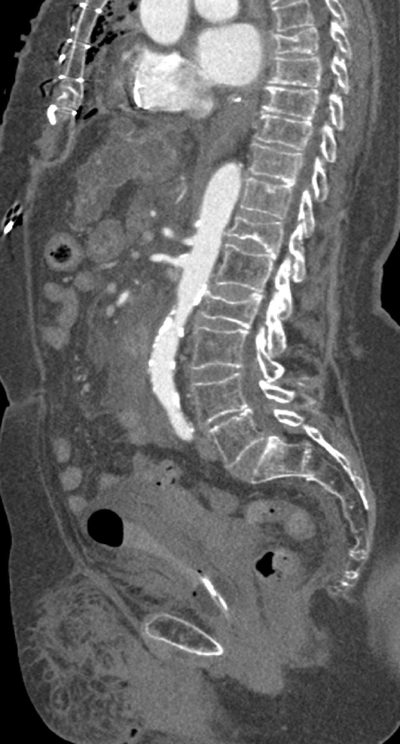

Figure 6

Parasagittal image of the contrast-enhanced aorta.